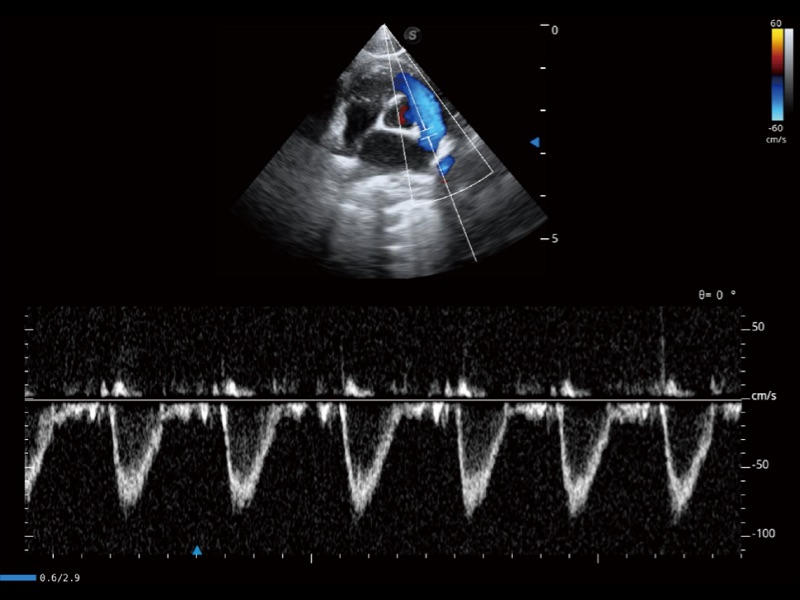

能够基于左心室壁追踪和辛普森法,自动计算射血分数,支持多个可移动点描迹,与手动测量相比,极大节省了动物医生的时间和精力。

通过360度任意调节3条M型取样线,在同一心动周期上观察心脏不同位置的运动曲线,得到准确的心功能测量数据,有效评估心肌运动及左心室功能。

实时用颜色表示心肌组织运动,观察和定量组织的运动情况,对快速检测与评估心肌的灌注和活性、电传导及心肌收缩和舒张功能等均能提供重要的诊断信息。